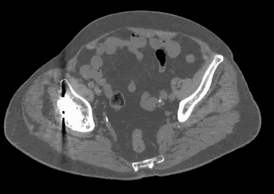

在介入手术室,我可以完成肿瘤患者的氩氦刀治疗、粒子植入放射治疗,医生们通过选购的配件,可以在手术室直接操控CT,实时看到CT图像和MPR图像,从而更快更准确的完成手术。